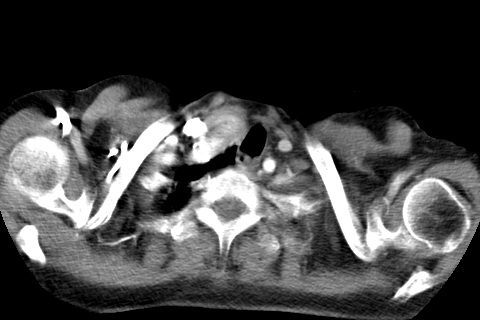

标题: CT23982:女67岁,胸部扫描时发现,甲状腺瘤? [打印本页]

标题: CT23982:女67岁,胸部扫描时发现,甲状腺瘤?

右侧甲状腺腺瘤!支持!不排除甲状腺癌可能!建议手术切除!

右侧甲状腺占位性病变,性质待定(甲状腺腺瘤?);建议:必要时行进一步检查。

右侧甲状腺占位性病变,性质待定(甲状腺腺瘤?);

右侧甲状腺占位性病变,性质待定(甲状腺腺瘤?);建议穿刺活检。

右侧甲状腺占位性病变,甲状腺腺瘤可能,建议穿刺活检。